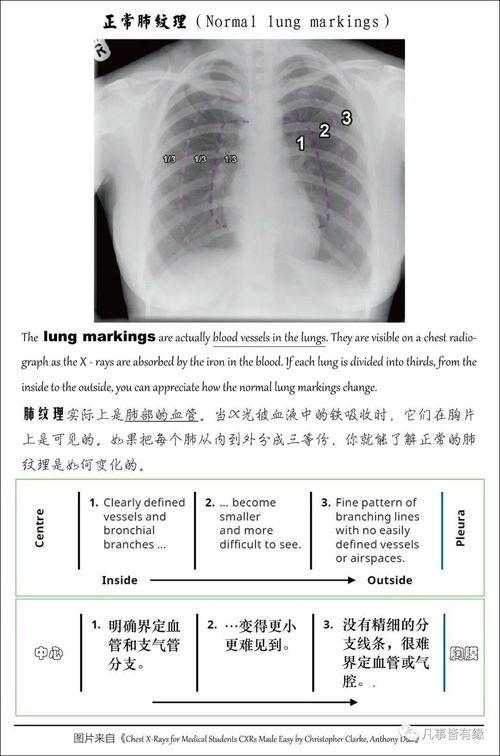

首先,得先弄清楚什么是胸片。胸片,顾名思义,就是通过X射线对人体胸部进行拍摄的一种医学影像检查。它能够清晰地显示出心脏、肺部、纵隔等器官的结构和形态,对于诊断各种胸部疾病有着至关重要的作用。